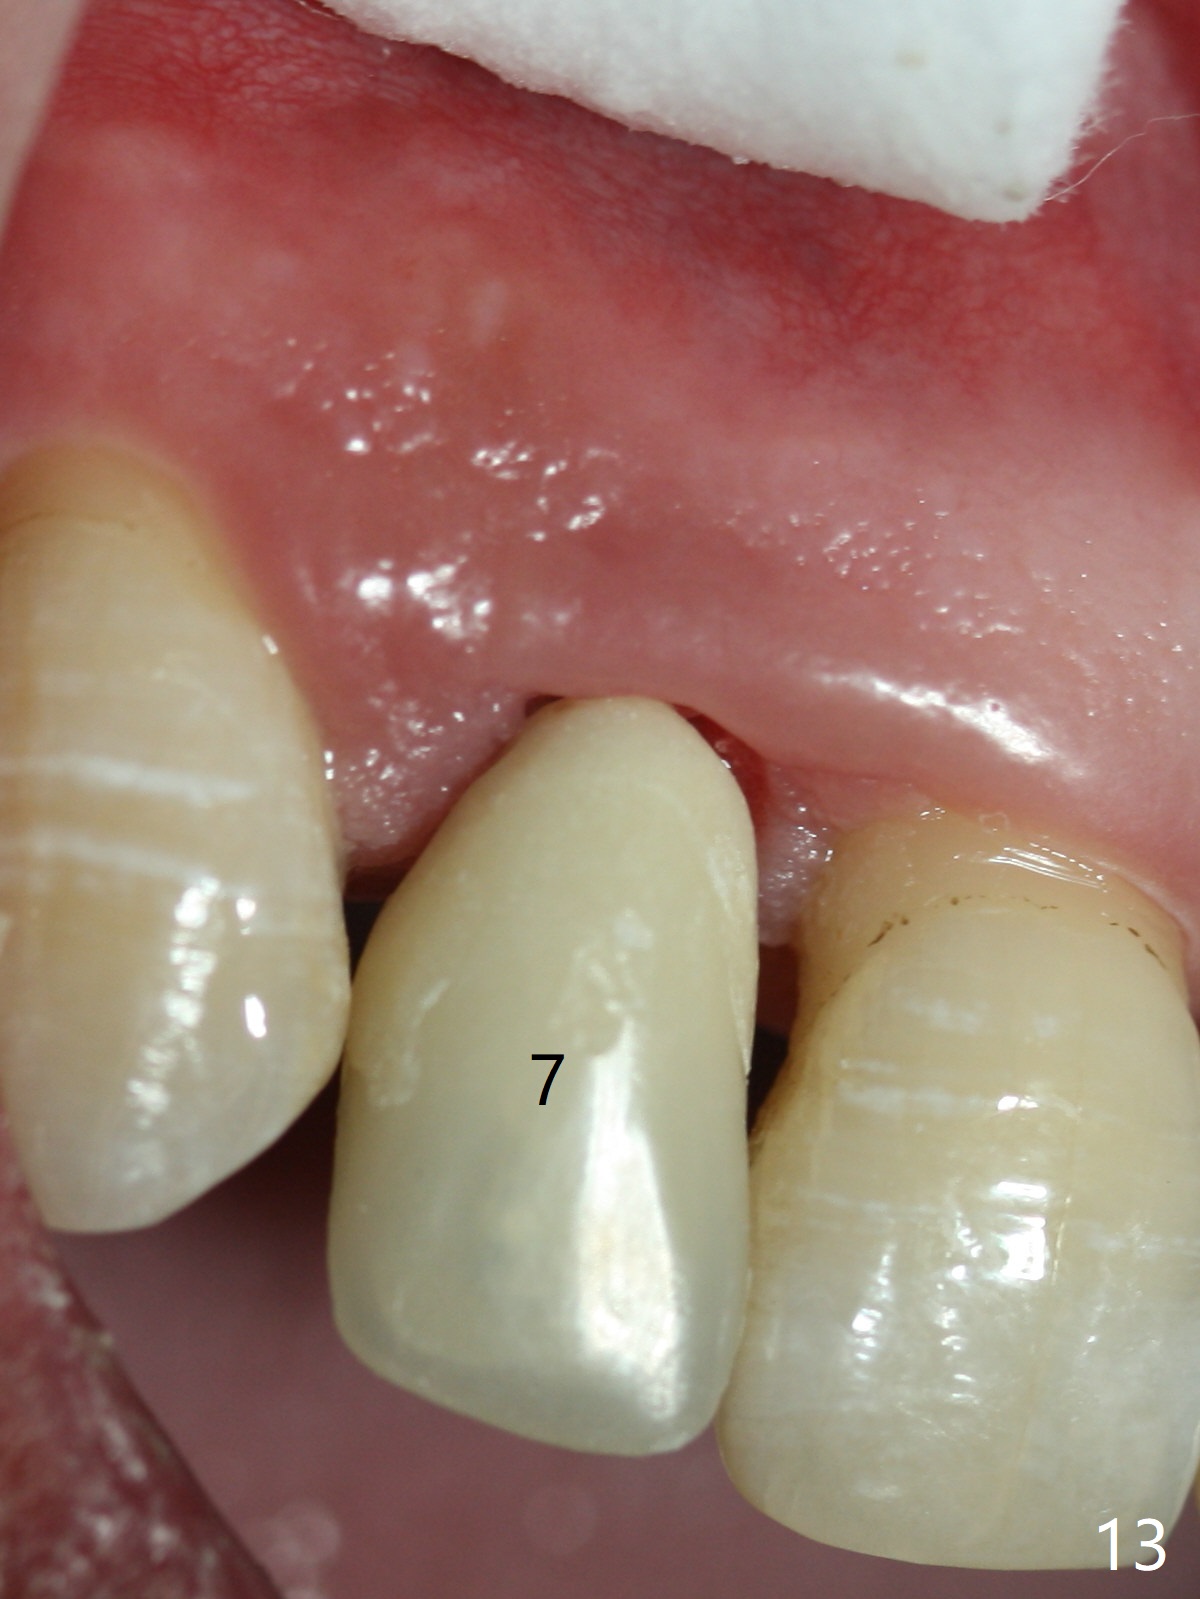

The patient returns 8 days postop, uncomfortable with overhang in the provisional (Fig.10 *). The sockets appear to be healing with loose bone graft (Fig.11) when the provisional is removed for trimming (Fig.12). Six (for #7,13) and seven (#9-11,15) months postop, the soft (Fig.13,17) and hard (Fig.14-16,18) tissues heal. It appears that the trajectory at #9,11 and 13 should be changed by using angled abutments (Fig.18,19 (panoramic X-ray taken 2 months earlier)) before provisional and final restoration.